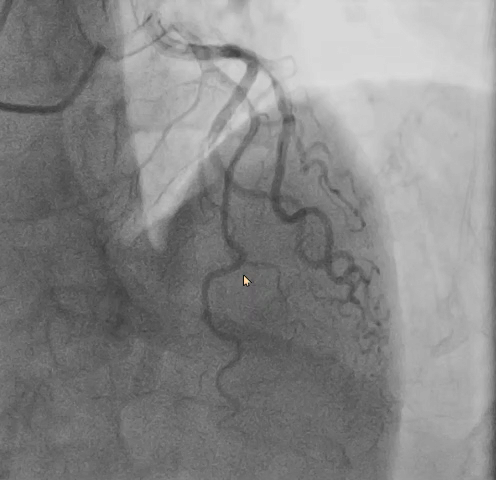

• AV31瓣膜腰部直径约27mm,可能会增加左冠阻塞风险,故讨论策略决定在植入前先行左冠保护,保证冠脉安全。

行左冠保护,预置左冠球囊

冠脉造影评估灌注后撤出球囊,血压未回升,给予升压药物仍无法回复血压。